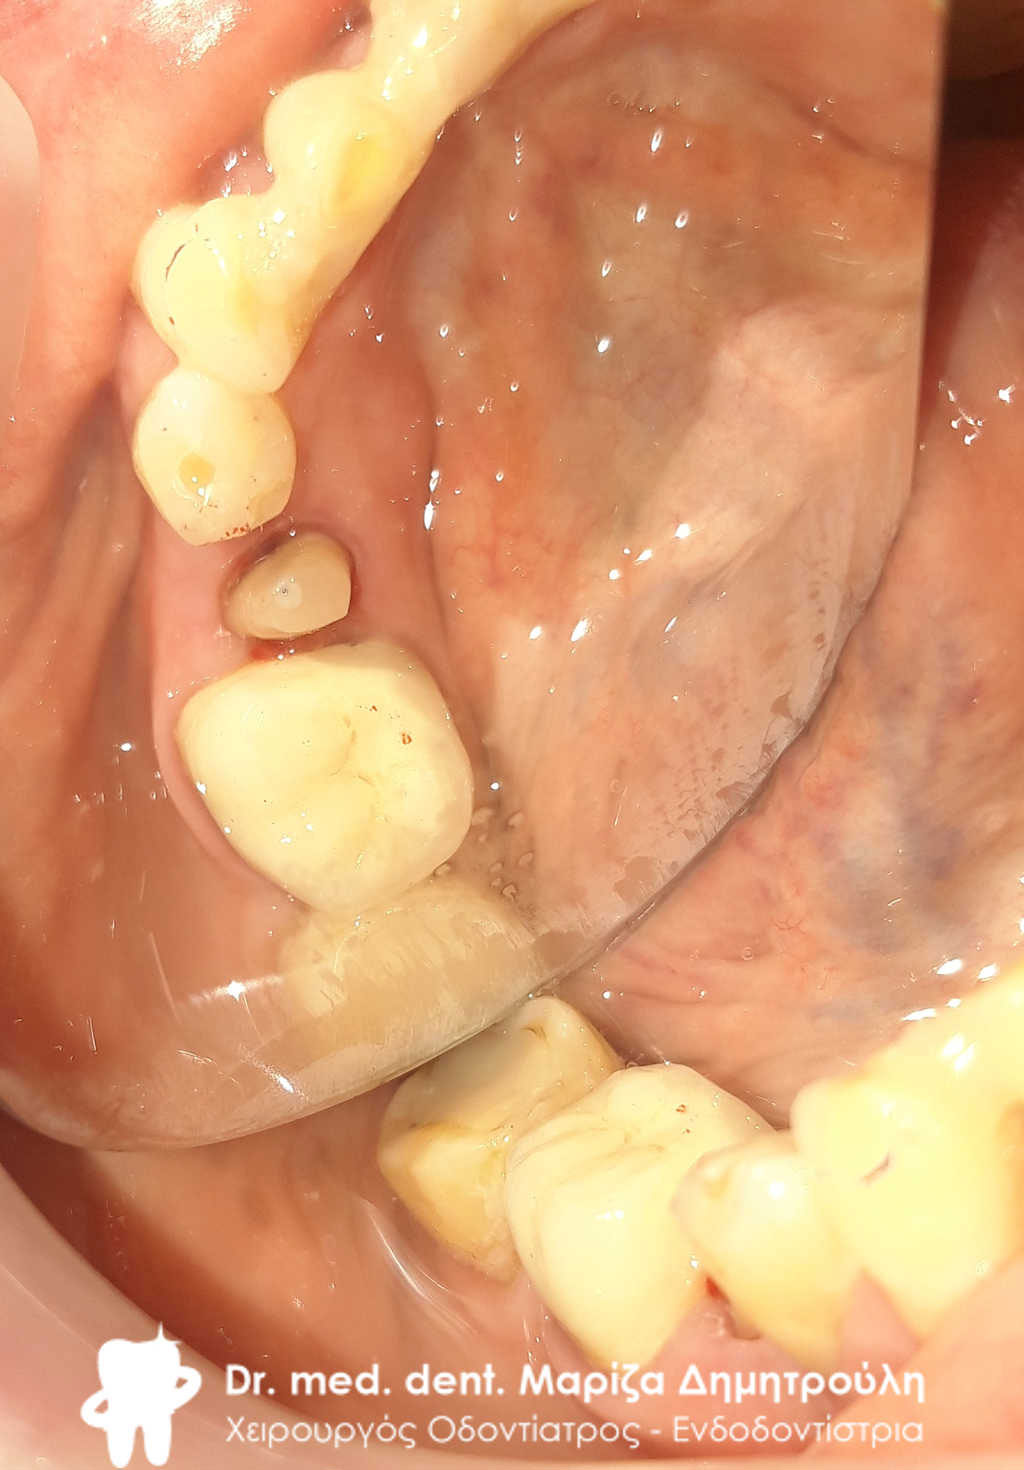

Περιστατικό – Ολοκεραμική θήκη ζιρκονίου στον αριστερο γομφίο της κάτω γνάθου

Ο πρώτος γόμφιος στην αριστερή πλευρά της κάτω γνάθου είχε απονευρωθεί στο παρελθόν. Ο ασθενής δεν θέλησε να καλύψει το δόντι με θήκη, ώστε να είναι πλήρως προστατευμένο με αποτέλεσμα το δόντι να σπάσει (όπως φαίνεται στην αρχική εικόνα). Η λύση θεραπείας ήταν η κατασκευή στεφάνης δοντιού, αφού προηγουμένως το δόντι τροχίστηκε καταλλήλως και ο οδοντοτεχνίτης κατασκεύασε την ολοκεραμική θήκη ζιρκονίου.

Το δόντι είναι πλέον πλήρως προστατευμένο και μπορεί να αντέξει στο πέρασμα των χρόνων.

ΠΡΙΝ

ΜΕΤΑ